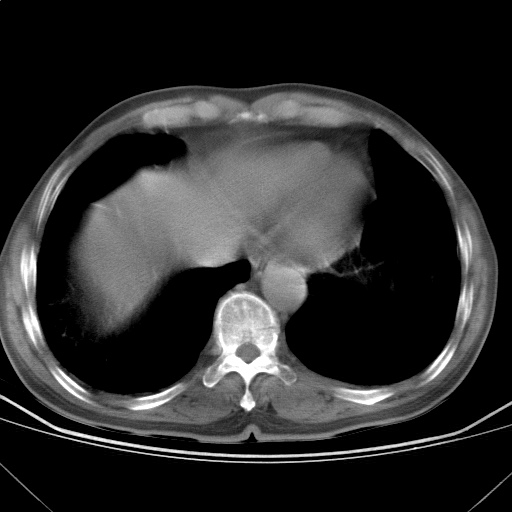

以下是引用随光逐影在2009-5-1 13:53:00的发言:[br]考虑为:1)两肺血行播散型肺结核;2)右肺下叶炎症感染。3)右侧胸膜增厚。